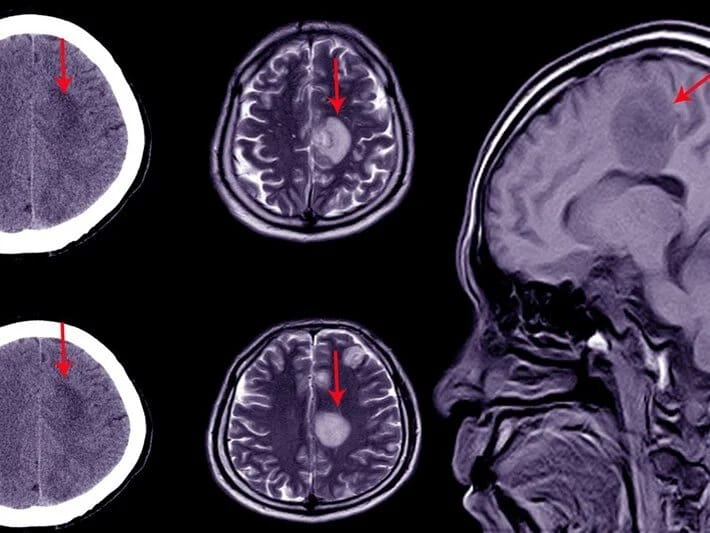

Alimləri təəccübləndirən hadisə: Beyninin 90 faizi olmayan insan!